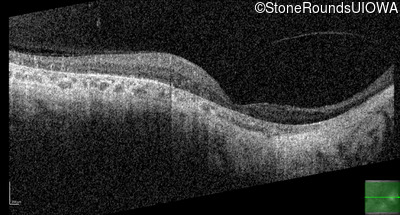

This 46 year old man first had difficulty driving at night in his mid-thirties. Clinically focused genetic testing for Choroideremia was negative.

| XL Choroideremia | CHM | Insertion of 212.3kb of Chr. 3 in intron 2 (IVS2+15,016 ins 212.3kb) | XL |